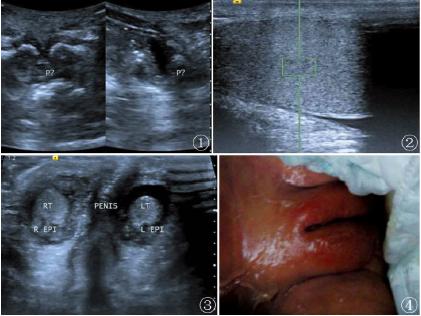

图2睾丸的剪切波值测量;图3双侧睾丸及阴茎回声;图4患儿女性外阴表现